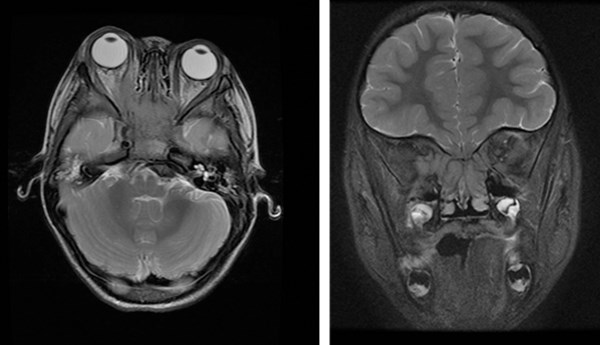

The posterior pole is not visualized on ophthalmologic evaluation under sedation. Emergent MRI of the brain and orbits reveals an intracranial expansive, erosive mass within the sphenoid body with local extension into right orbital apex and its musculature. Signal characteristics of the mass (low T1 and T2 with significant diffusion restriction) and extension into the orbital musculature are highly suggestive of the tumor’s lymphoid nature. (Images 1, 2).